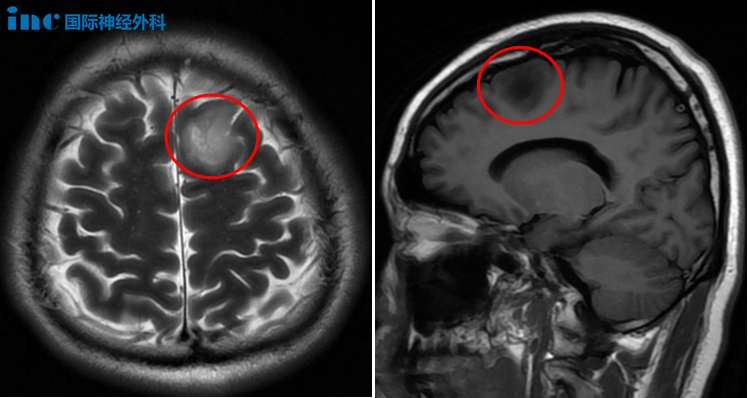

2025年,申先生在例行体检中意外发现胶质瘤。当时他并未出现任何临床症状,但仍果断接受了开颅手术。手术实现了肿瘤的扩大切除,术后病理学检查结果确认为WHO 2级少突胶质细胞瘤。面对深爱的家人,这次劫后余生的经历让他对人生规划产生了新的思考。他决定将更多时间用于陪伴家人,同时迎接新生命的到来,用心享受美好的生活。

9月上旬,他与巴教授进行了线上面对面咨询。正是这次沟通,让他确信找到了理想的主刀医生。“巴教授详细分析了手术切除范围以及并发症风险等所有细节。我能感受到他的那种匠心精神和精益求精,以及充分的人文关怀。”巴教授判断这是低级别胶质瘤,他有信心实现全切甚至扩大切除,且大概率避免并发症。

决策既定,便迅速执行。2025年9月,申先生在首都医科大学附属北京天坛医院国际部由巴特朗菲教授亲自主刀接受了手术。手术结果十分理想:肿瘤得以扩大全切(扩大3-5毫米),病理诊断为WHO 2级少突胶质细胞瘤,预后极佳。更让家属欣慰的是,术后申先生无需进入ICU,当天即恢复意识,肢体活动、语言功能都保持正常。